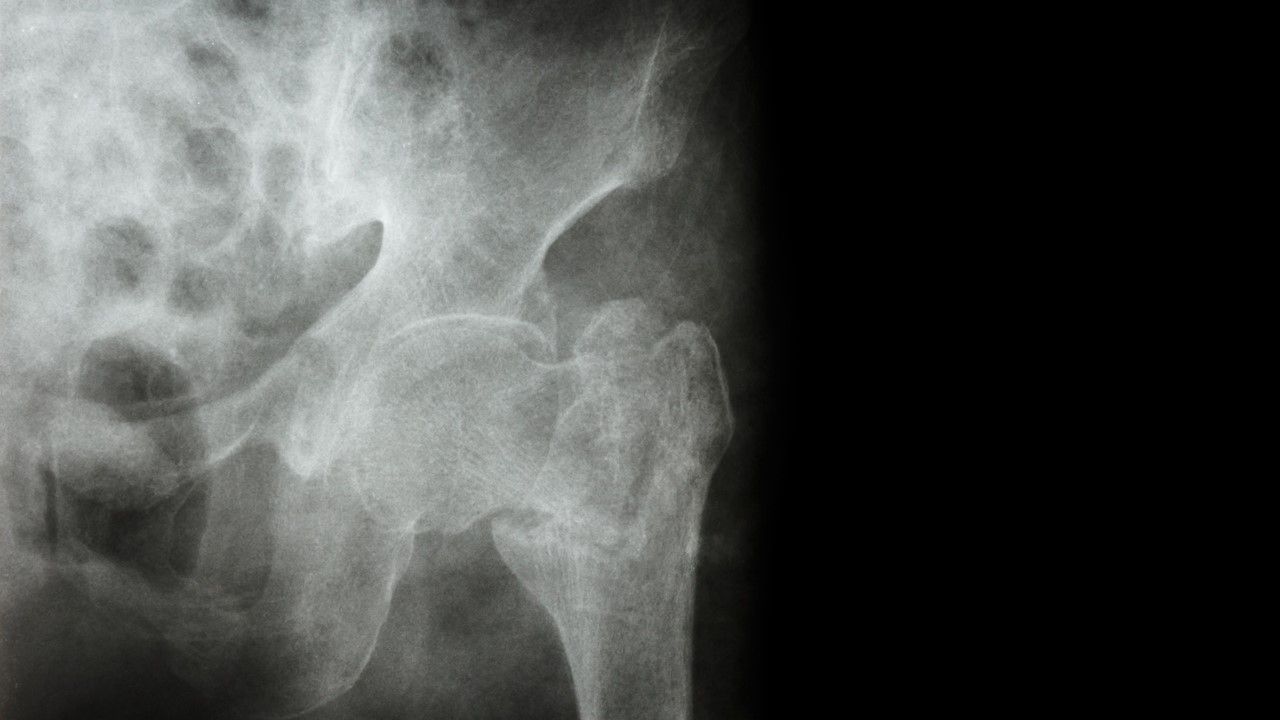

The use of tramadol in older patients is associated with a higher risk of hip fracture compared with the use of codeine or commonly used nonsteroidal anti-inflammatory drugs (NSAIDs), say researchers recently writing in in the Journal of Bone and Mineral Research.